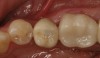

The cemented implant crown, which has now been converted to a screw-retained version, can be placed on the implant fixture. The screw is then tightened to the manufacturer’s recommended amount of torque. A piece of Teflon tape or cotton is placed into the screw-access hole. The same ceramic primer is positioned around the opening of the screw-access hole and dried followed by the application of an adhesive bonding agent. The adhesive is then light polymerized followed by the application of a resin composite that matches the shade of the crown. After it is light polymerized, the occlusion of the resin composite “patch” is verified and then smoothed and polished (Figure 19 through Figure 21).

Fig 19. Lingual view of the screw-retained implant crown after placement of the composite “patch.”

Figure 19

Fig 20. Facial view of screw-retained implant crown.

Figure 20

Fig 21. Occlusal view of the screw-retained implant crown.

Figure 21